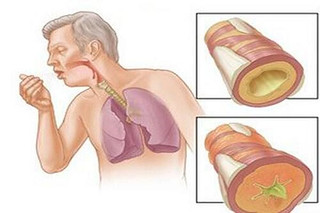

Khi mắc bệnh lao, trong cơ thể mỗi người có hàng triệu trực khuẩn lao, các vi khuẩn này theo đàm, nước bọt…bắn ra môi trường không khí. Theo ước tính, khi ho, khạc nhổ một bệnh nhân lao cho ra ngoài hơn 3000 vi khuẩn lao, khi hắt hơi con số này lên tới 1.000.000 vi khuẩn. Các vi khuẩn này bay lơ lửng trong môi trường không khí, người bình thường hít phải sẽ nhiễm bệnh. Vì vậy, lao là bệnh có khả năng lây nhiễm vô cùng cao, mặt khác, đối với những người có sức đề kháng yếu, hệ miễn dịch suy giảm, sẽ tạo điều kiện thuận lợi cho lao bùng phát, nhất là với những người đã điều trị lao, phổi bị tổn thương, cộng với các yếu tố khác tác động như sức khỏe, dinh dưỡng, môi trường…khiến lao tái phát lại là điều hoàn toàn dễ hiểu.

Dấu hiệu thường gặp của lao